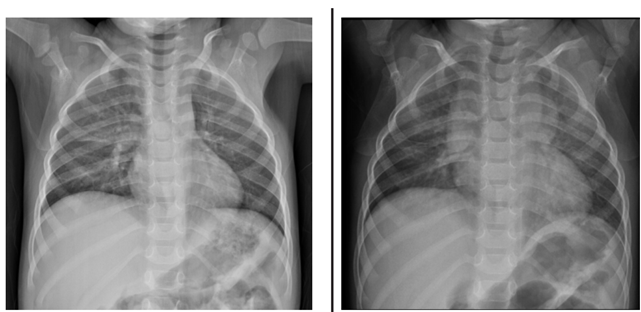

Menino de 2 anos e 6 meses, com história de tosse, dispneia, choro, inapetência e febre há 4 dias, realizou radiografa de tórax (primeira imagem). Após o exame, a mãe recebeu receita médica com medicações para a criança tomar durante 2 semanas, com orientação de repetir a radiografa (segunda imagem) 1 semana após o término do tratamento.

Considerando os dados clínicos e as radiografas acima, analise as afirmativas abaixo e dê os valores Verdadeiro (V) ou Falso (F).

( ) O diagnóstico inicial mais provável é pneumonia, tanto pelos dados clínicos como pela presença de opacidades pulmonares no terço médio à direita na primeira imagem, porém o achado de massa mediastinal na segunda imagem torna a hipótese de pneumonia menos provável.

( ) No exame de controle evolutivo realizado 3 semanas após o primeiro atendimento houve o aparecimento de consolidações pulmonares supra-hilares bilaterais, indicando piora radiológica.

( ) Após a análise das duas radiografas, pode-se chegar à conclusão de que trata-se de um quadro de hiperplasia tímica rebote em criança em processo de recuperação de pneumonia.

Assinale a alternativa que apresenta a sequência correta de cima para baixo.